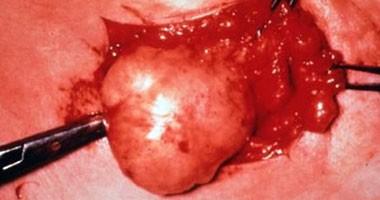

أولها استئصال الورم جراحيا عن طريق الكحت الجراحى وتفريغ التجويف الورمى بداخل العظمة، ولكن تلك الطريقة ينتج عنها بقايا ميكروسكوبية، وبالتالى يحدث نمو وتكاثر للخلايا الورمية مما يترتب عليه حدوث ارتجاع للورم وهى نسبة ليست بالقليلة فى جراحات أورام العظام الحميدة إذ تصل إلى حوالى 10-25%، وأحيانا تصل إلى 50% فى ورم الخلايا العملاقة الحميدة.

والخطوة الثانية وهى المعالجة الموضعية بالمحفزات الكيميائية أو الفيزيقية للقضاء على البقايا الميكروسكوبية، ولضمان القضاء على الخلايا الورمية، وبالتالى تقليل نسبة ارتجاع الورم.

ويقول الدكتور محمد إنه خلال العقدين الماضيين كان أشهر تلك المحفزات هو استخدام الفينول الثلاثى لكى مكان التجويف الورمى بعد الكحت الجراحى، وكانت نسبة ارتجاع الأورام من 5: 7%، ولكن فى السنوات الأخيرة تم استخدام غاز النيتروجين السائل، ولكن باحتياطات معينة للمحافظة على الأنسجة المحيطة للتجويف الورمى، حيث إنه يقوم بكى والقضاء على الخلايا الورمية باختراق أكثر من واحد سنتيمتر، وبالتالى تقليل نسبة ارتجاع الأورام لأقل من 1% وهى نسبة ممتازة مقارنة بالكحت الجراحى فقط.